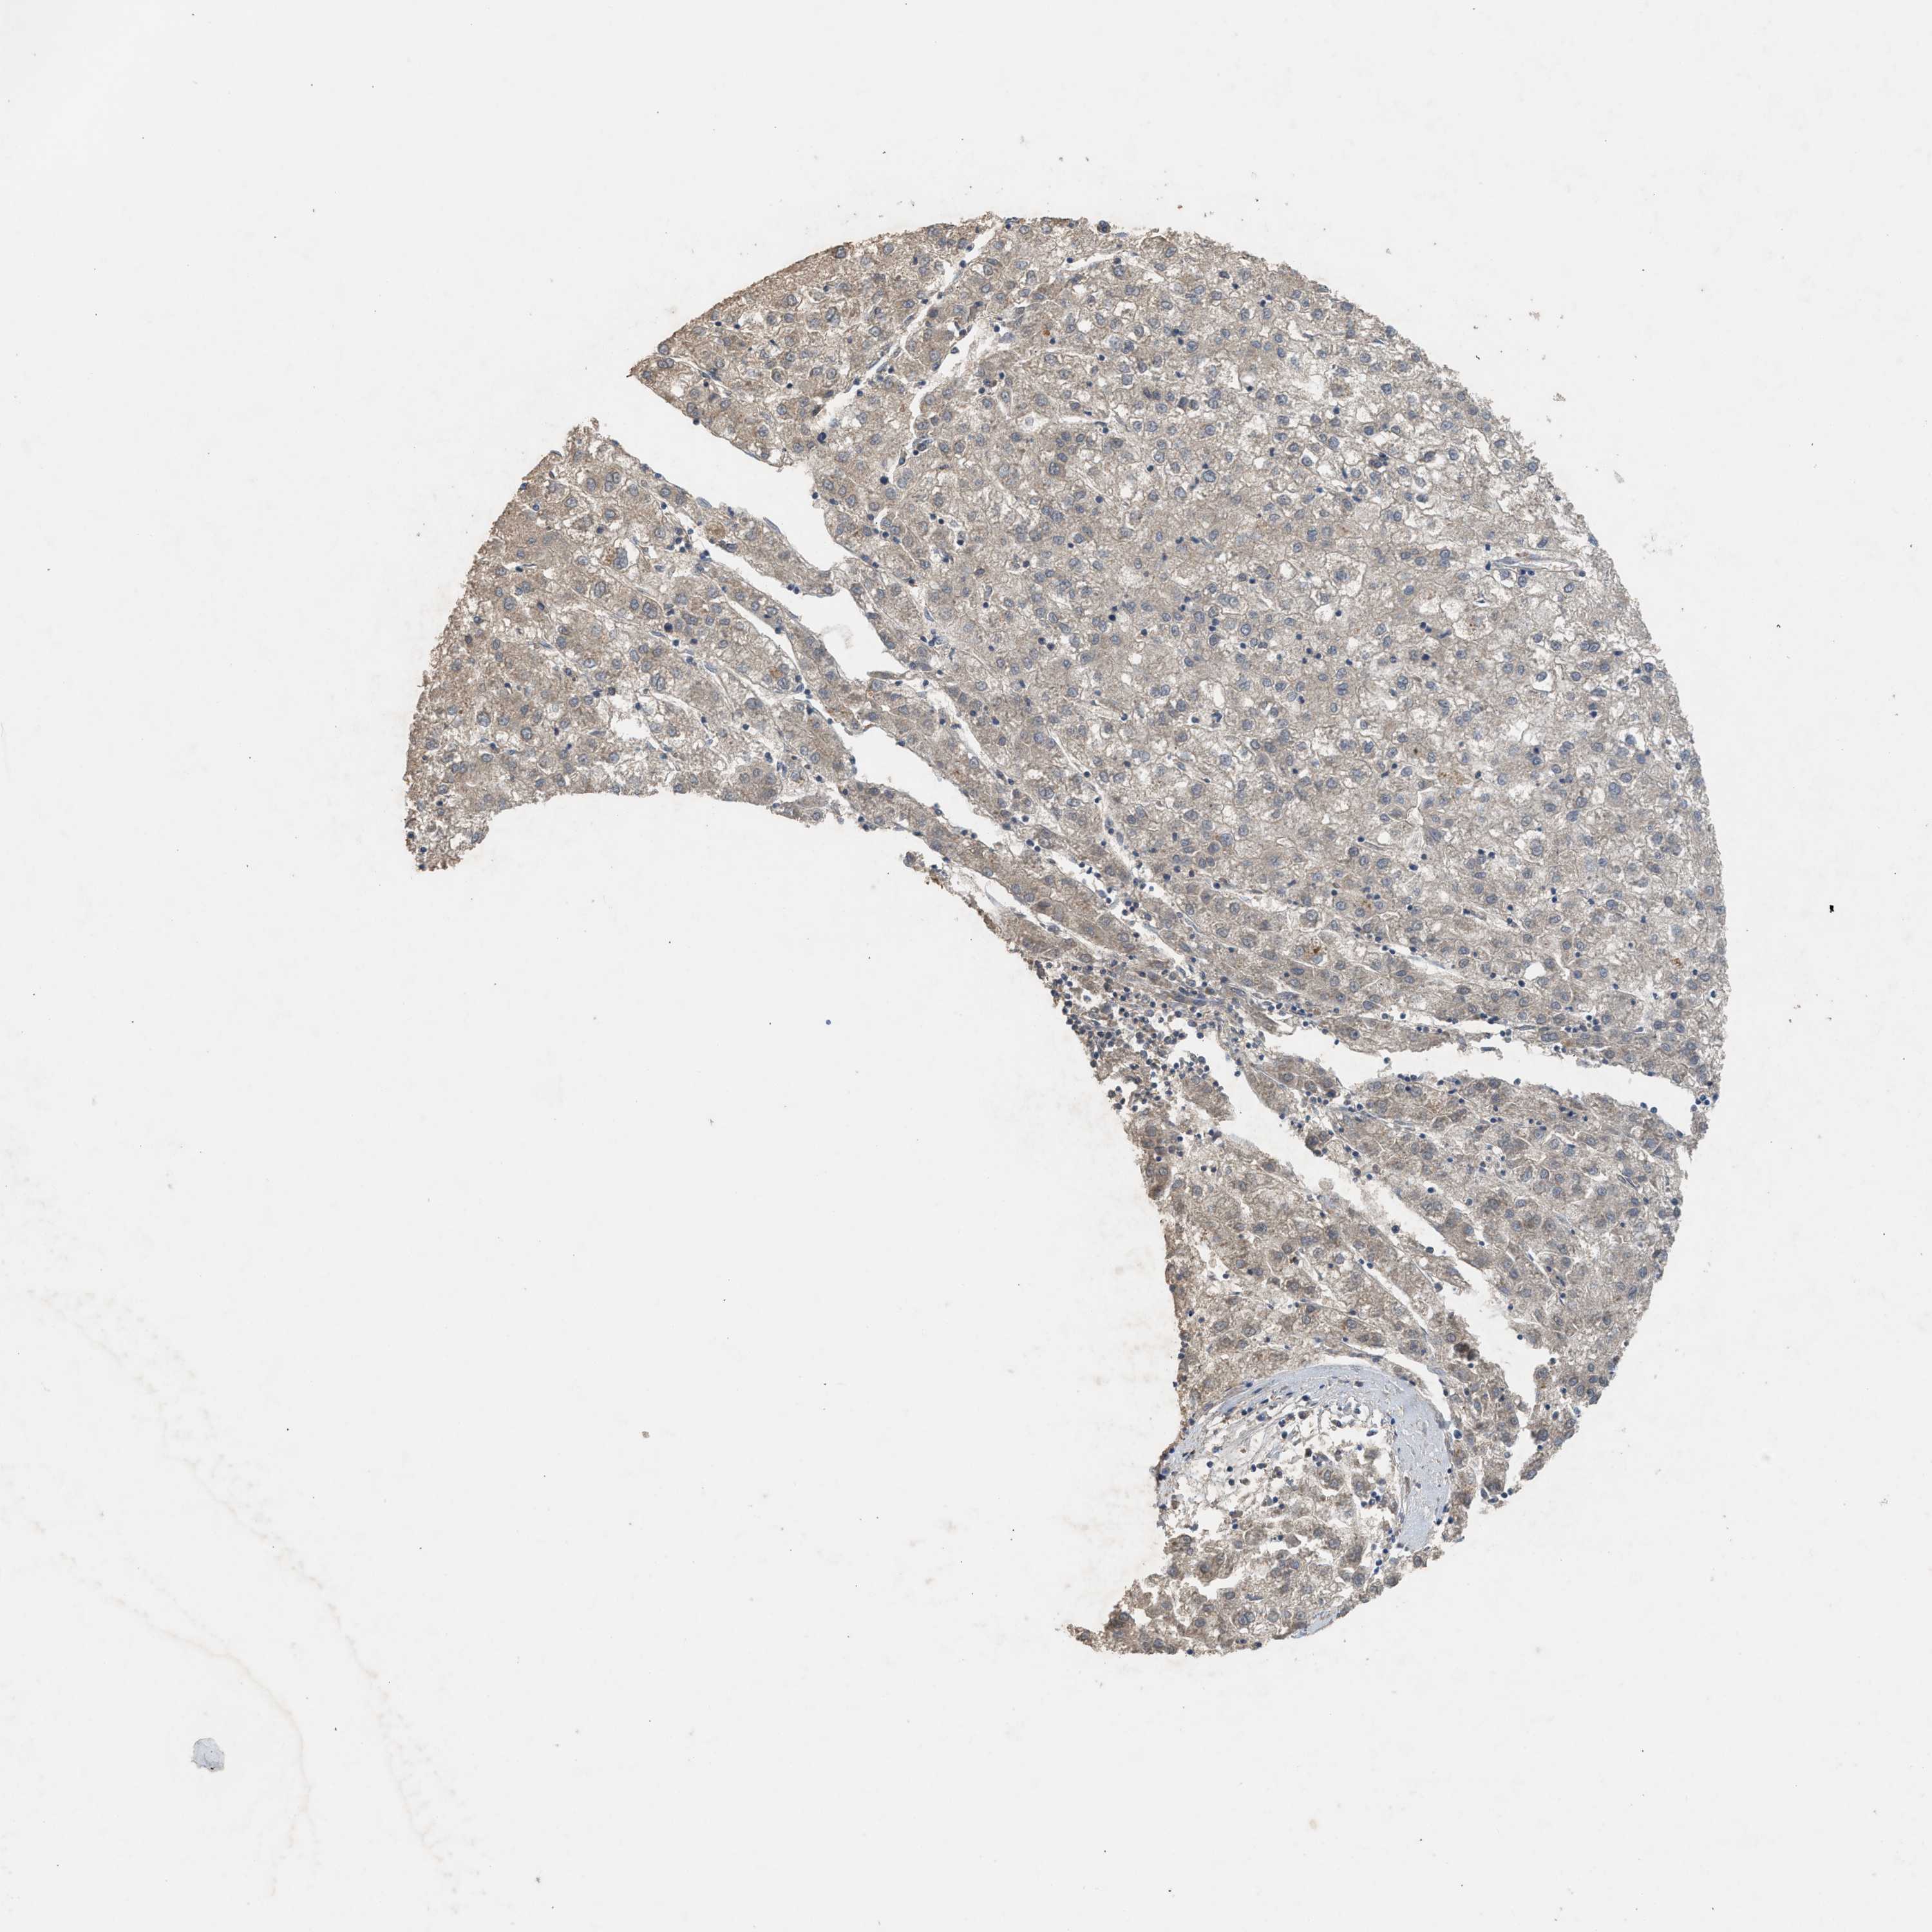

LIVER CANCER - Protein expressioni

A mouse-over function shows sample information and annotation data. Click on an image to view it in a full screen mode. Samples can be filtered based on level of antibody staining by selecting one or several of the following categories: high, medium, low and not detected. The assay and annotation is described here.

Note that samples used for immunohistochemistry by the Human Protein Atlas do not correspond to samples in the TCGA dataset.

Antibody stainingi

Antibody staining in the annotated cell types in the current human tissue is reported as not detected, low, medium, or high, based on conventional immunohistochemistry profiling in selected tissues. This score is based on the combination of the staining intensity and fraction of stained cells.

Each image is clickable and will lead to virtual microscopy that enables deeper exploration of all samples and also displays staining intensity scores, fraction scores and subcellular localization as well as patient and tissue information for each sample.

Antibody HPA008237

Antibody CAB017181

Staining

High

Medium

Low

Not detected

Intensity

Strong

Moderate

Weak

Negative

Quantity

>75%

75%-25%

<25%

None

Location

Nuclear

Cytoplasmic/membranous

Cytoplasmic/membranous,nuclear

Cholangiocarcinoma

Carcinoma, Hepatocellular, NOS